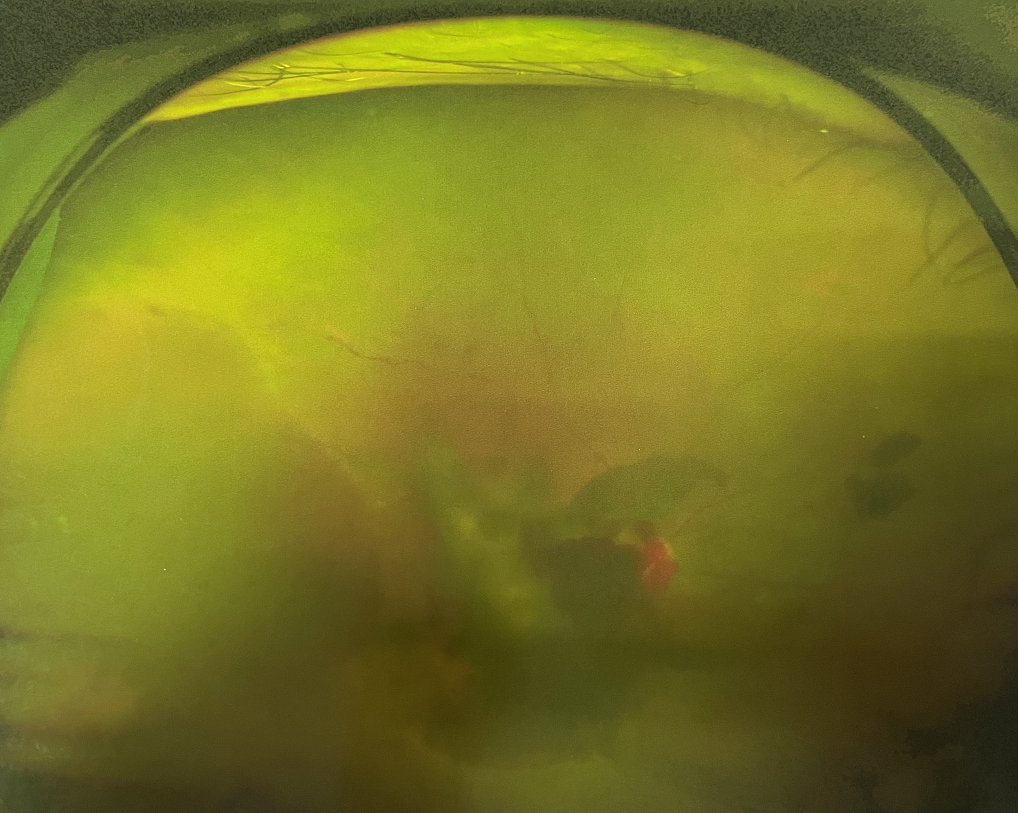

眼底出血是指眼內(nèi)視網(wǎng)膜出血,或玻璃體內(nèi)出血。眼底位于眼睛深處,所以這類出血只靠肉眼是看不到的,早期可能不紅、不痛、不癢,需通過專業(yè)的眼底檢查才可看到,往往短期內(nèi)就可造成視力驟降甚至失明!

同樣的,眼底出血也是一種癥狀,而非病種。誘發(fā)眼底出血的原因很多,常見的有全身性血管病和血液病、視網(wǎng)膜血管異常、機械性阻塞、炎癥性疾病或免疫復(fù)合物侵犯血管壁等。

一只眼睛眼底出血